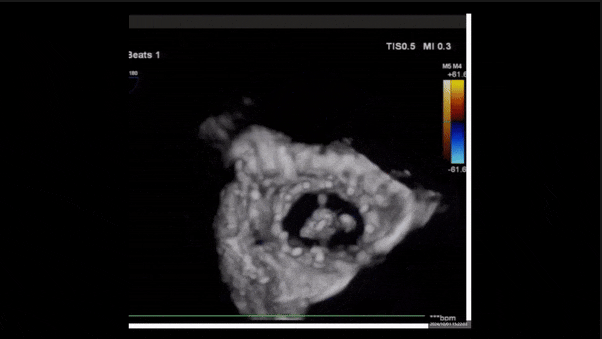

術(shù)后三維超聲

術(shù)后即刻經(jīng)食道超聲可見,三尖瓣假體瓣膜位置合適,牛心包瓣葉運(yùn)動狀態(tài)良好,開閉正常,瓣周及瓣葉對合緣處未見明顯返流,心電圖及心包狀態(tài)較術(shù)前無明顯變化。